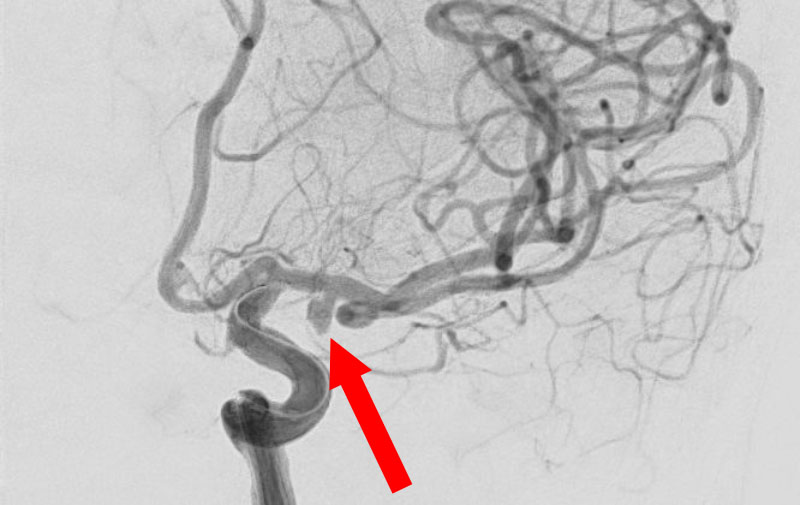

'25年11月

左内頚動脈脳動脈瘤

60代

大阪府の病院

No.1595 手術前

No.1595 手術中

No.1595 手術後